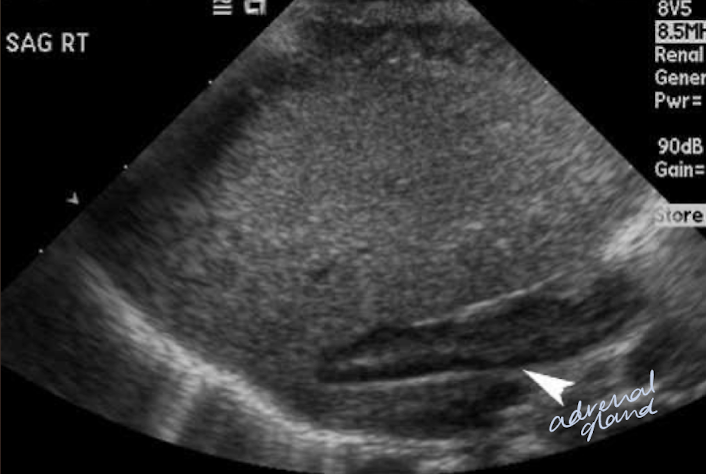

adrenal glands

endocrine organ

could possibly be seen with US in infants and young children

consists of an independently functioning cortex and medulla

supplied by suprarenal arteries

drained by suprarenal vein